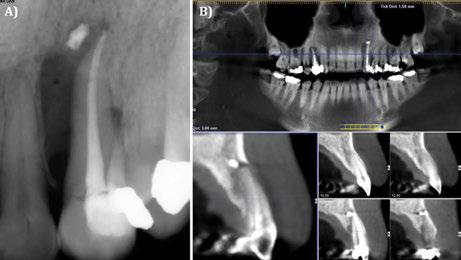

Figura 1. Caso clínico con membrana no reabsorbible (Goretex®). A) Situación radiográfica (2D) basal. B) Situación radiográfica (3D) basal.

Figura 2. Caso clínico con membrana no reabsorbible (Goretex®).